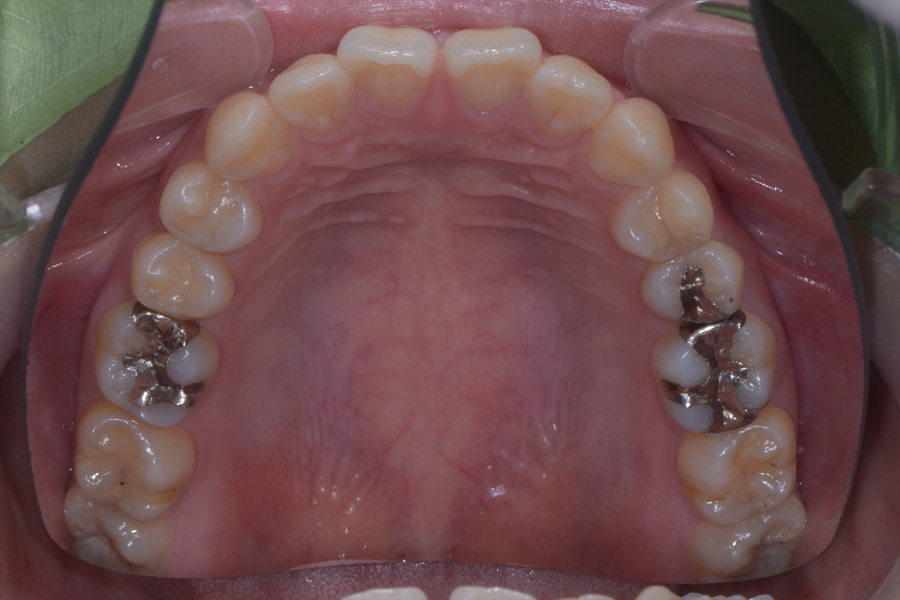

治療前

主訴 出っ歯とすきっ歯を治したい

治療内容 上顎ラビアル矯正(表側矯正)